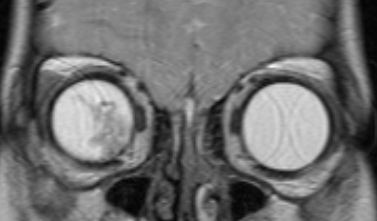

МРТ головного мозга и орбит

Магнитно-резонансная томография дает возможность в деталях увидеть распространение процесса за пределы глазного яблока и точно определить стадию болезни. Такое исследование нужно проводить всем пациентам, у которых ретинобластома диагностирована впервые. Контраст при МРТ повышает информативность.

![Визуализация ретинобластомы с помощью МРТ. Фронтальное изображение орбит. Клиническая группа D]()

Рис. 4. Визуализация ретинобластомы с помощью МРТ. Фронтальное изображение орбит. Клиническая группа D